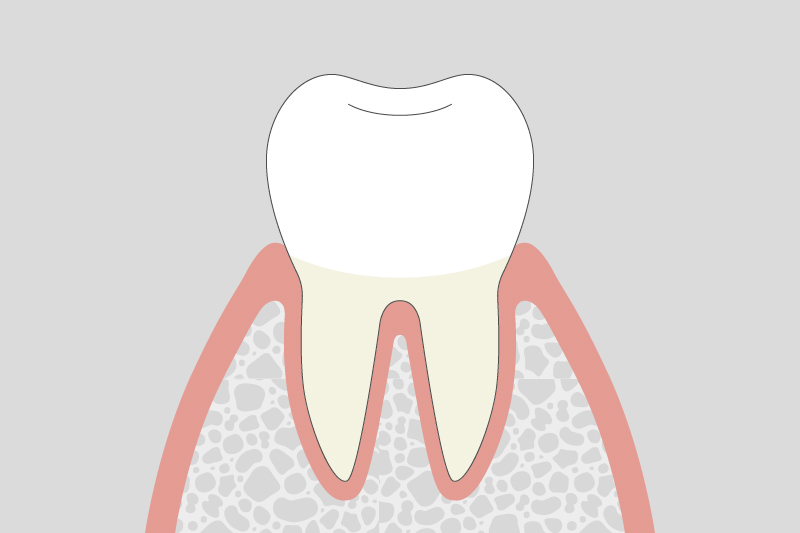

01.

歯肉炎(軽度)

歯ぐきが赤く腫れ、歯磨きの際に出血しやすくなります。まだ歯を支える骨への影響は少ない段階です。